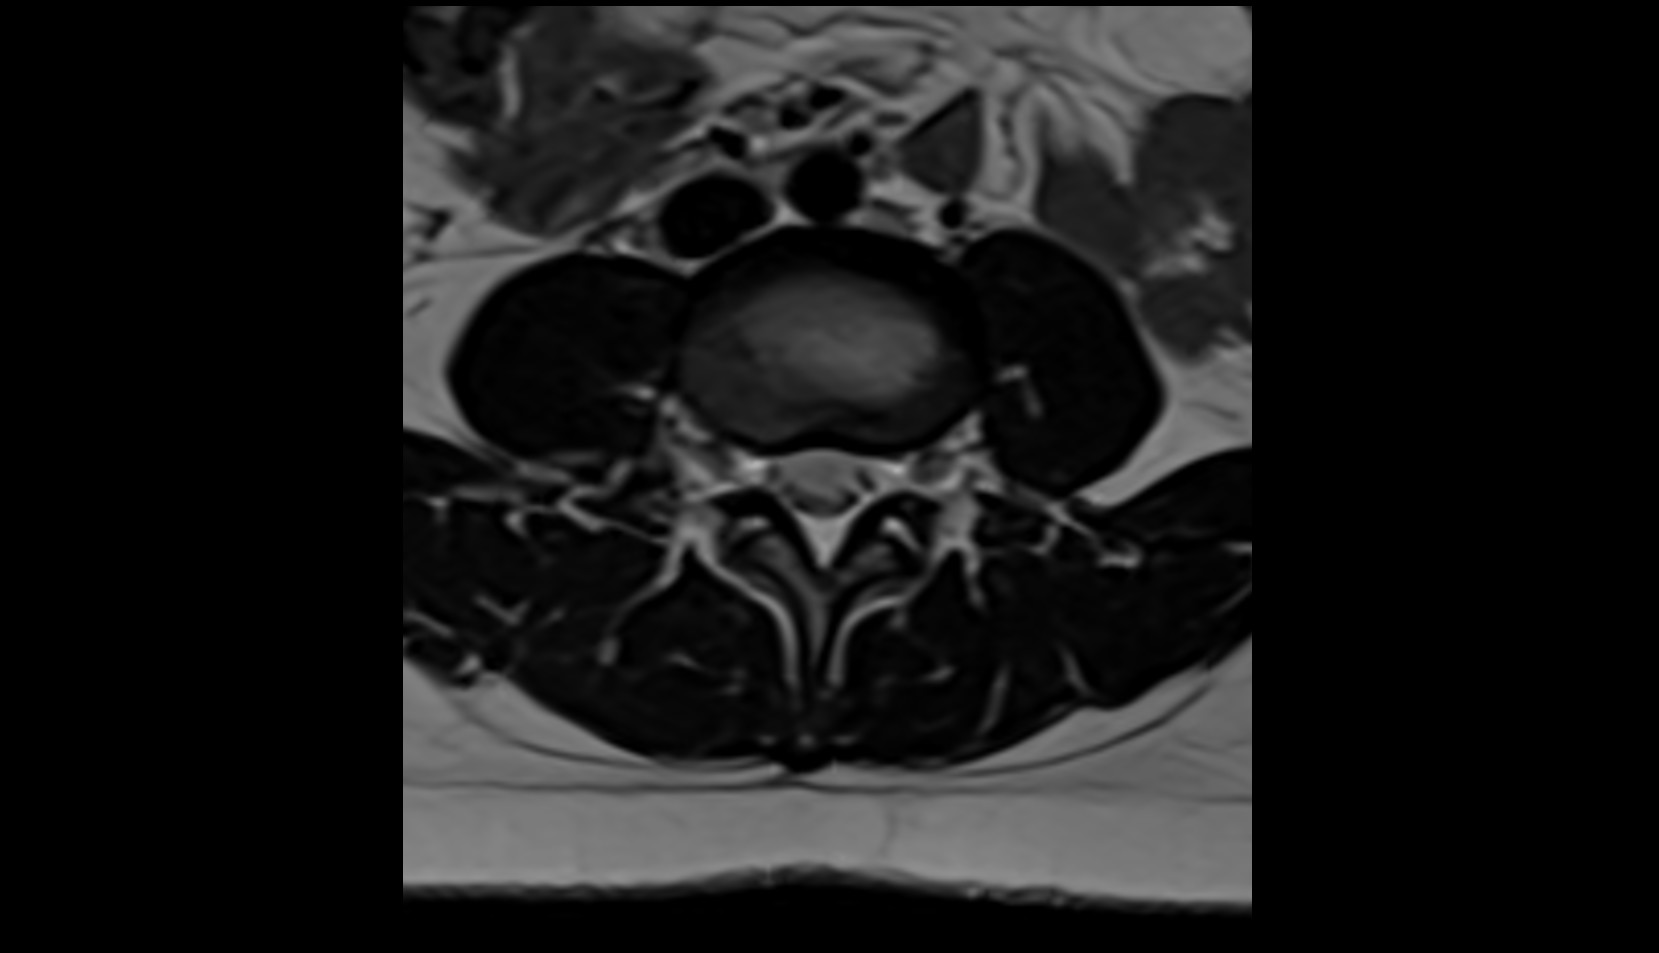

- Cauda equina

- Conus medullaris